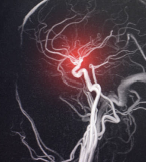

뇌경색은 뇌혈관이 막히면서 해당 부위에 혈류가 차단되어 뇌세포가 괴사되는 질환이며,

초기에 증상을 알아채고 3시간 내 병원에 도착하면 생명과 후유증 모두 지킬 수 있습니다.